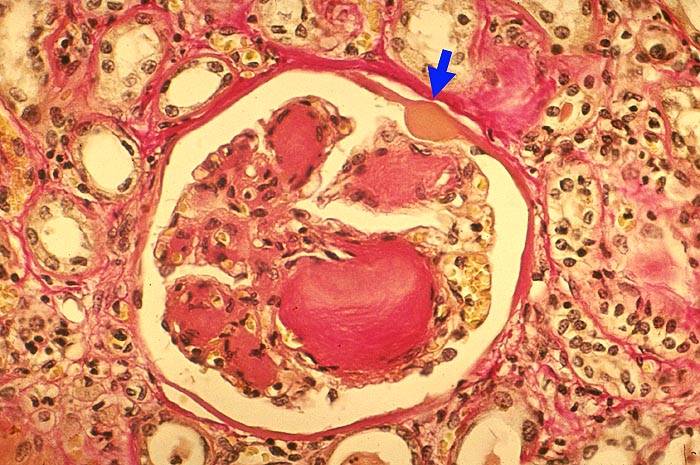

Noduläre Glomerulosklerose Kimmelstiel-Wilson

Das Mesangium ist knotig verbreitert. Der grösste Knoten zeigt eine lamelläre Schichtung. Die Glomerulusschlingen über diesem Knoten sind teils leicht dilatiert. In der Bowman'Kapselbasalmembran ist ein ► Kapseltropfen erkennbar.

Noduläre Glomerulosklerose: Zwiebelschalenartig geschichtete, azelluläre Knoten im Mesangium. Primär leichte Hyperzellularität der Noduli. Im Allgemeinen folgt die noduläre Glomerulosklerose der diffusen Glomerulosklerose vor allem bei Typ I Diabetes. Dabei oft multiple kleine Knoten im Mesangium. Beim NIDDM gelegentlich einzelne sehr grosse Noduli mit nur wenigen Glomeruli ohne relevante diffuse Glomerulosklerose. Die noduläre Glomerulosklerose ist aber nicht einfach eine besonders schwere Form der diffusen, sondern wahrscheinlich eine unabhängige Erkrankung mit verschiedener Pathogenese.